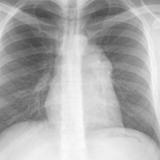

Case 9 Thymoma PA

Date: 04/04/2010

Views: 3182